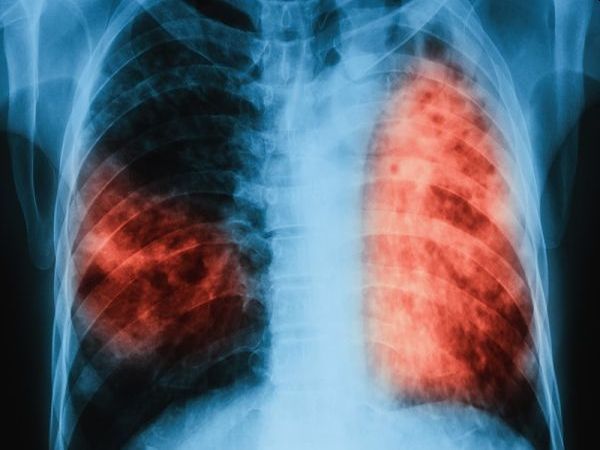

Днес, 19 юни 2023 г., за втори път през тази година ще се проведат безплатни прегледи за туберкулоза в лечебни заведения за диагностика и лечение на туберкулозата в областните градове на страната. Прегледите са част от кампанията „Седмица на отворените врати”, която се организира в изпълнение на Националната програма за превенция и контрол на туберкулозата на Министерството на здравеопазването, чиято цел е намаляване заболеваемостта от туберкулоза в страната, съобщават от ведомството.

Туберкулозата е лечима и предотвратима, стига да бъде открита навреме и да бъде проведено качествено лечение, припомнят от МЗ.